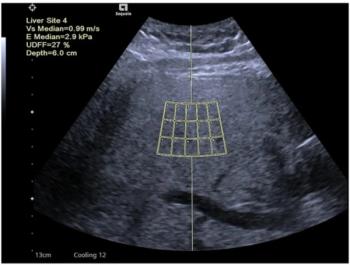

Although not new to the RSNA exhibit floor, Hitachi's Sono Elastography merits mention. The technology, shown in 2004 and this year as part of the HI Vision 8500 ultrasound system, measures the relative stiffness of tissue, overlaying this information as a color map onto the standard B-mode image. This perspective offers new insights into the physical properties of tumors and masses, possibly unveiling lesions previously undetectable, according to the company.